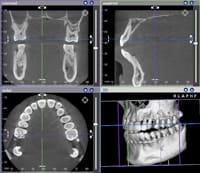

従来のX線写真で得られる情報は二次元の平面的なものでしたが、歯科用CTでは、短時間で三次元画像を構築できるので、より正確な多くの情報が得られることになりました。

そのため、矯正歯科治療を始めるにあたって、たとえば、骨の中に埋もれて生えてこない歯(埋伏歯)の位置を確認したり、歯周病の患者さんの歯槽骨の状態の確認などを正確に行うことができ、これらの情報は治療方針を立てる上で重要になります。